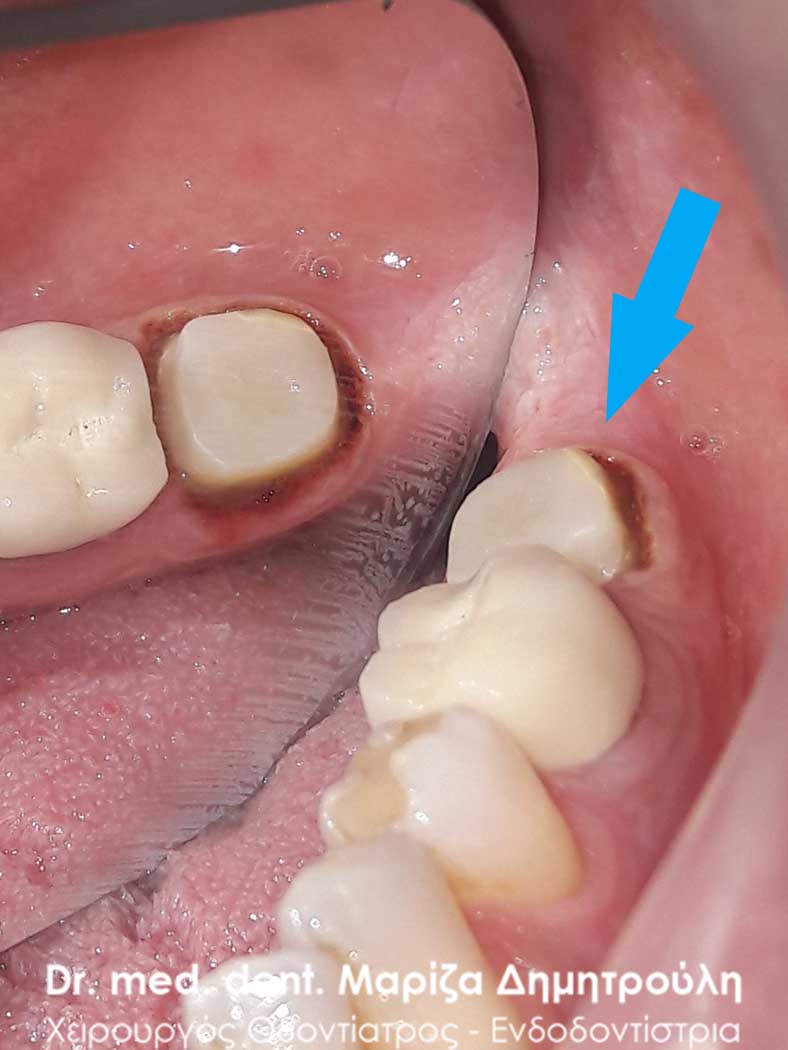

Αρχική κλινική εικόνα του μεγάλου οδοντικού ελλείμματος